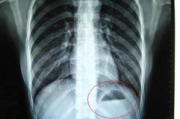

胸透照片的重要性与应用解析-医学诊断中的关键角色 在当今医疗诊断领域,胸透照片作为一项重要的检查手段,被广泛应用于肺部疾病的早期发现和治疗。本文将深入探讨胸透照片的重要性、拍摄技巧、分析方法以及在临床中的应用,... 服饰 admin 19 2026-01-23